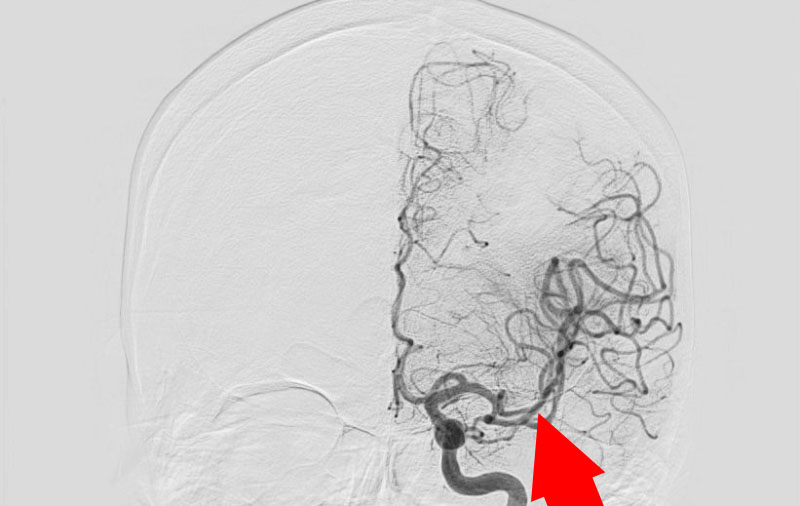

脳動静脈奇形

70代

大阪府の病院

No.1182 手術前

No.1182 手術中

No.1182 手術後